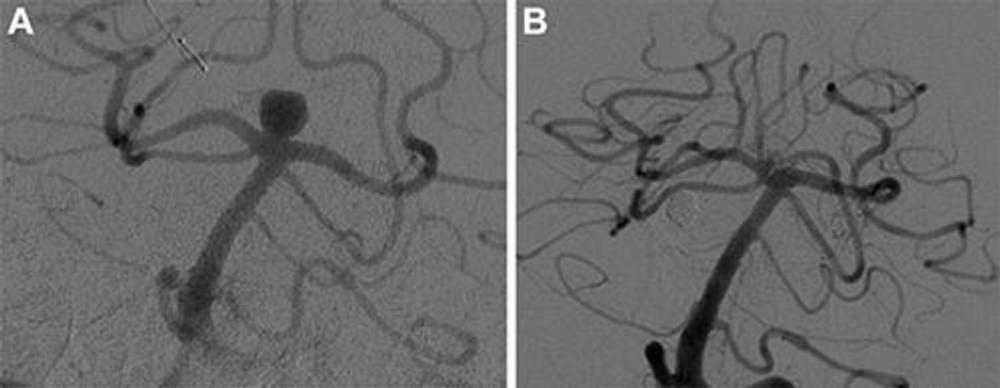

Figure 3. Digital subtraction angiography images show posterior communicating artery aneurysm (A) before and (B) at last follow-up after Woven EndoBridge device placement.